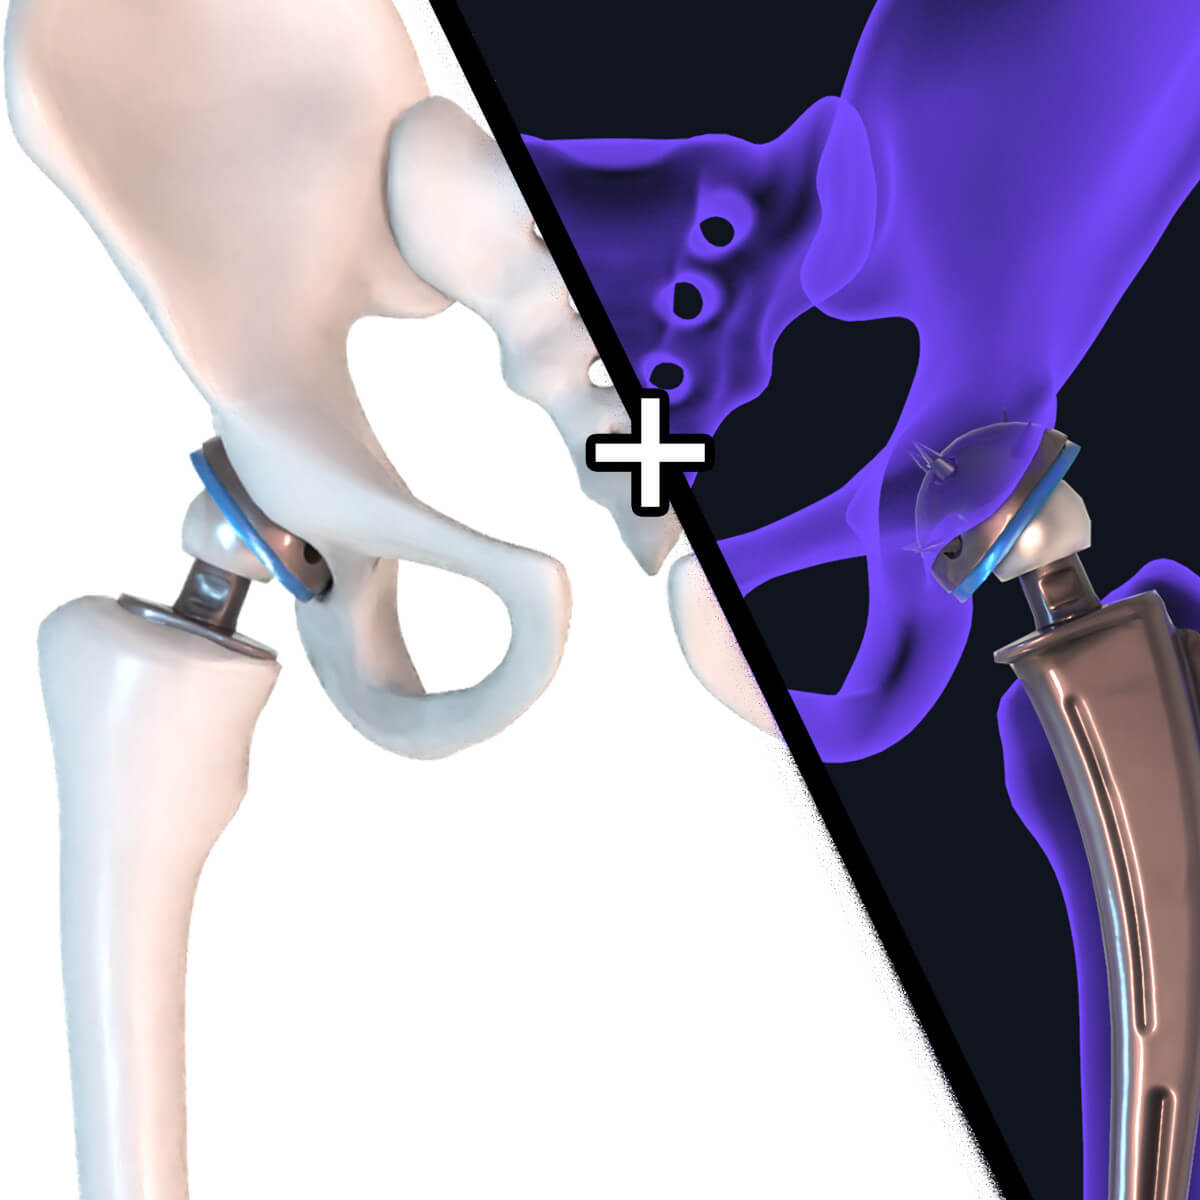

Замена таз сустава

Замена таз сустава 113 фотографий